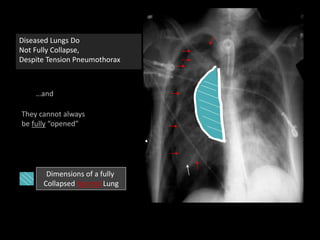

Diseased Lungs Do

Not Fully Collapse,

Despite Tension Pneumothorax

…and

They cannot always

be fully “opened”

Dimensions of a fully

Collapsed Normal Lung